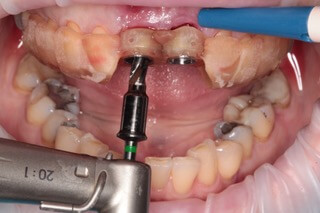

V ďalšom kroku sme virtuálne vložili implantáty v správnej protetickej polohe, navrhli šablónu pre ich zavedenie, namodelovali individuálne abutmenty a korunky. Kompletné dáta sme exportovali pre frézovanie a 3D tlač. V laboratóriu sa pomocou 3D tlačiarne vytlačila chirurgická šablóna, ktorá nám slúži na presné zavedenie implantátov – použili sme implantačný systém Dentium Super Line. Následne boli vyfrézované zirkonové abutmenty a plastové dočasné korunky.

Ukážka - navigovaná chirurgia z praxe